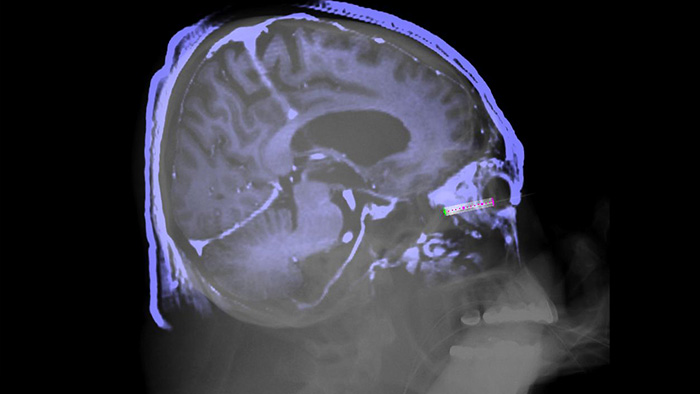

XperGuide biedt live 3D-beeldgeleiding van naalden, zodat u percutane naaldprocedures in de Hybrid OR kunt uitvoeren. Het legt live fluoroscopie- en 3D-beeldgegevens van weke delen van eerder verworven CT- of MR-scans of Philips XperCT over elkaar en biedt zo informatie over het naaldtraject en het doel.